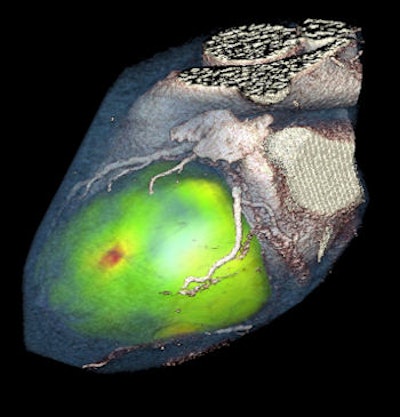

At the recent congress of the European Society of Cardiology (ESC), Dr. Aju Paul Pazhenkottil, a cardiac imaging specialist from Zurich University Hospital, demonstrated the predictive value of SPECT/CT for fusing myocardial perfusion imaging from SPECT with the complementary anatomical CT image.

Pazhenkottil is the lead author of "Prognostic value of cardiac hybrid imaging integrating single-photon emission computed tomography with coronary computed tomography angiography," published in June 2011 in the European Heart Journal (Vol. 32:12, pp. 1465-1471), which was among the first studies to demonstrate the predictive value of combining perfusion and anatomical data.

For the study, 324 patients were divided into three types according to the results of the hybrid exam, a matched group with a finding of stenosis by coronary CT angiography (CTA) and a matching reversible SPECT defect, patients with unmatched coronary CTA and SPECT finding, and then patients found to be normal by both coronary CTA and SPECT.

At a median follow-up of 2.8 years, a corresponding matched hybrid image finding was associated with a significantly higher incidence of death or myocardial infarction (MI), proving to be an independent predictor for major adverse cardiac events. The annual death/MI rate was 6.0% for patients with matched coronary CTA-SPECT findings, 2.8% for those with unmatched results and 1.3%, among those with normal findings.